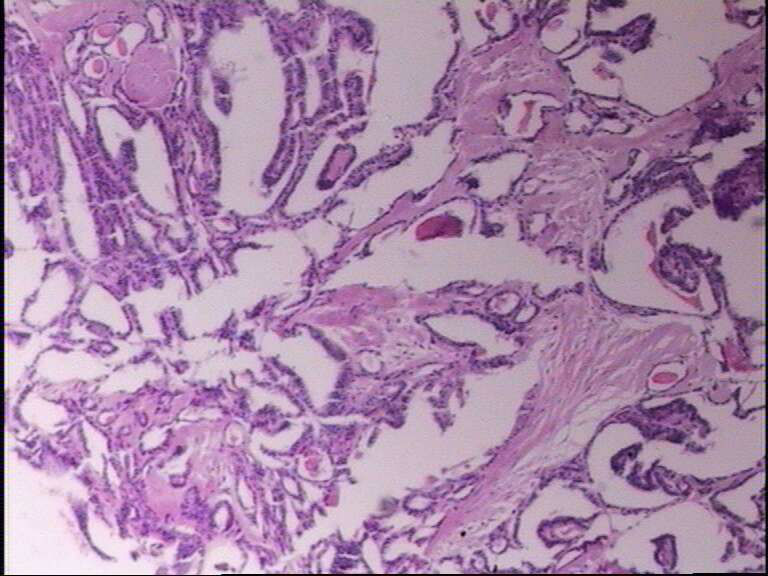

女43岁,甲状腺肿物